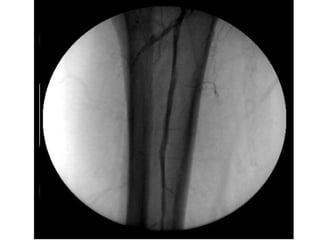

ISQUÉMIA CRÍTICA TRATAMENTO - Revascularização Cirurgia convencional Cirurgia endovascular - Proximal - Distal - Multisegmentar

ISQUÉMIA CRÍTICA TRATAMENTO- Revascularização Cirurgia convencional Cirurgia endovascular - Proximal - Distal - Multisegmentar